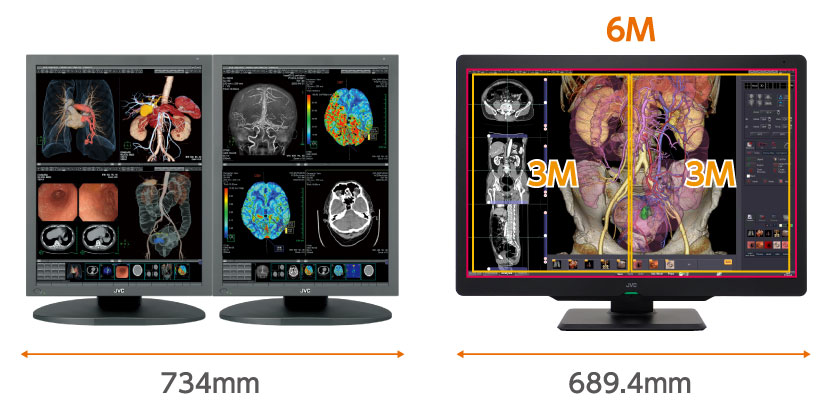

Bezramkowy ekran wielkoformatowy o powierzchni 30” i wysokiej rozdzielczości 6 milionów pikseli zmniejsza zmęczenie oczu zapewniając komfortowe warunki pracy. Monitor ten pozwala na swobodne wyświetlanie obok siebie nie tylko dwóch obrazów radiologicznych, ale także obrazów z innych modalności, takich jak CT, MR, USG czy patomorfologi. Ze względu na dużą powierzchnię monitora, układ wyświetlanych okien można dowolnie aranżować na potrzeby rożnych badań.

Oszczędność miejsca

30-calowy, kolorowy wyświetlacz LCD oferuje powierzchnię obrazowania odpowiadającą dwóm monitorom 3MP. Monitor CL-S600 umożliwia również efektywne zarządzanie przestrzenią roboczą i układem okien.

| Parametry fizyczne | Wymiary (szerokość x wysokość x głębokość) | 689,4 mm x 509,9~604,9 mm x 224,9 mm Bez podstawy 689,4 mm x 475,6 (484,9)mm x 85,7 mm |